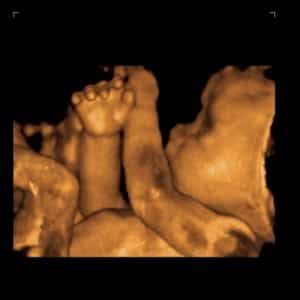

13. ¿Me darán alguna imagen?: El primer retrato de tu bebé en blanco y negro flotando en tu tripa será de lo más emocionante. En casi todos los centros suelen facilitar una copia de la ecografia, y en algunos incluso permiten grabar en vídeo la sesión. Pregunta a tu ginecólogo para llevar preparado un disco